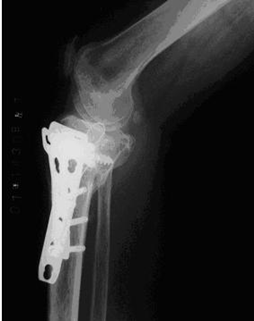

为了防止对胫骨平台骨折手术后延迟负重导致的骨折延迟愈合、关节僵直、肌肉萎缩、骨质疏松等并发症。我们在临床应用气压减重训练仪,采取早期个性化定量的减重负重训练治疗累及关节面的胫骨平台骨折。通过治疗取得良好疗效,患者的骨折愈合良好而没有出现关节面的塌陷,关节功能恢复正常(图1-3)。

图1.一例左膝胫骨平台骨折 图2.内固定术后的X线片表现